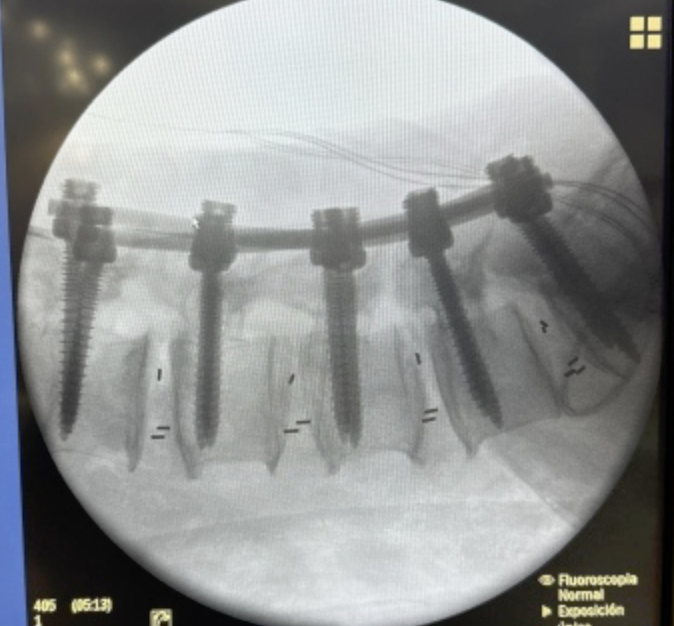

Cada procedimiento requiere una planificación detallada, basada en estudios de imagen y evaluación clínica, con el objetivo de lograr una descompresión adecuada de estructuras nerviosas y restaurar la estabilidad vertebral.

Se emplean técnicas quirúrgicas modernas, incluyendo abordajes mínimamente invasivos cuando son viables, lo que permite una recuperación más rápida y menor impacto en el paciente.

El enfoque está orientado a resultados funcionales, disminución del dolor y mejora significativa en la calidad de vida, siempre priorizando la seguridad y el bienestar del paciente.